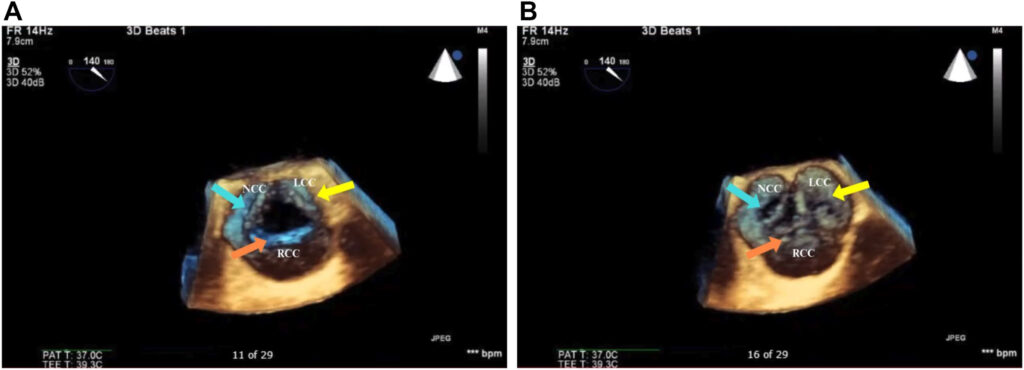

No terceiro dia de admissão, foi realizado ecocardiograma transtorácico cujo resultado demonstrou fração de ejeção (FE) de 60% e uma valva aórtica trivalvular com perfuração do folheto não coronariano e insuficiência aórtica (IAo).

Indicada abordagem cirúrgica e ecocardiograma transesofágico antes do procedimento mostrou prolapso do folheto coronariano direito, perfuração do folheto coronariano esquerdo e também no não coronariano, além de fluxo reverso holodiastólico em aorta descendente.